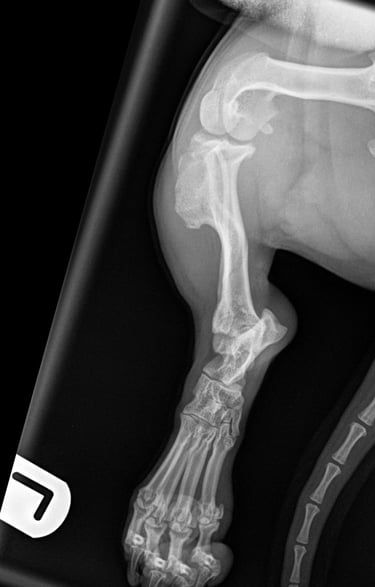

Tibia fracture - Mini Dachshund, 2y, female

This small and sweet 5.4 kg female patient sustained a lameness after playing in the garden allotment. Orthogonal radiographs revealed a surgical, long oblique spiral mid-diaphyseal fracture of the left tibia (Fig. 1 and 2).

Fig. 1